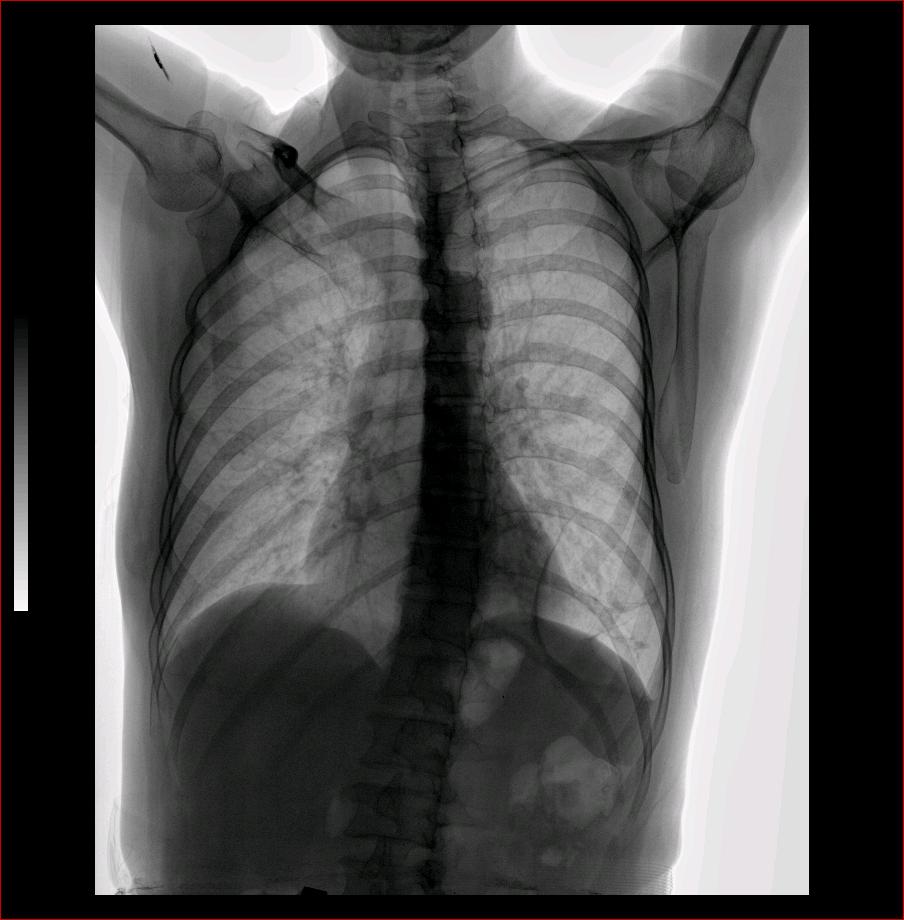

标题: CT9509:女,50岁,咳嗽,发热,38度, [打印本页]

标题: CT9509:女,50岁,咳嗽,发热,38度,

与x2653同一病人:http://www.radida.com/bbs/forum.php?mod=viewthread&tid=28727

左肺上叶舌段炎症,左肺下叶支气管扩张并感染

现有的征象提示左肺支扩并双肺炎症。至于隔离肺可以考虑但缺少证据。

双肺炎症;左下支扩并感染,肺隔离症待排

两肺炎症;左下支扩;左下肺副叶!

左肺舌叶及右肺下叶背段斑片状低密度影,左肺下叶内基底段网格状阴影,周围肺野透亮度增高,结合临床咳嗽、发热,38度,无咯血及反复感染病史,考虑双肺炎症,左下肺发育不良。建议抗炎治疗后复查或增强与左下肺隔离症鉴别。